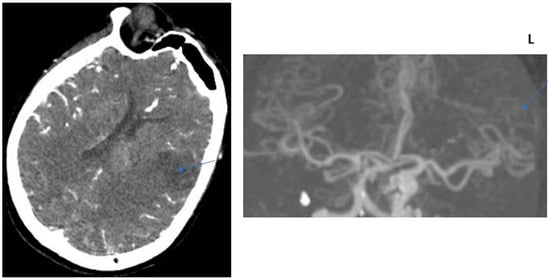

2.2. CT Protocol